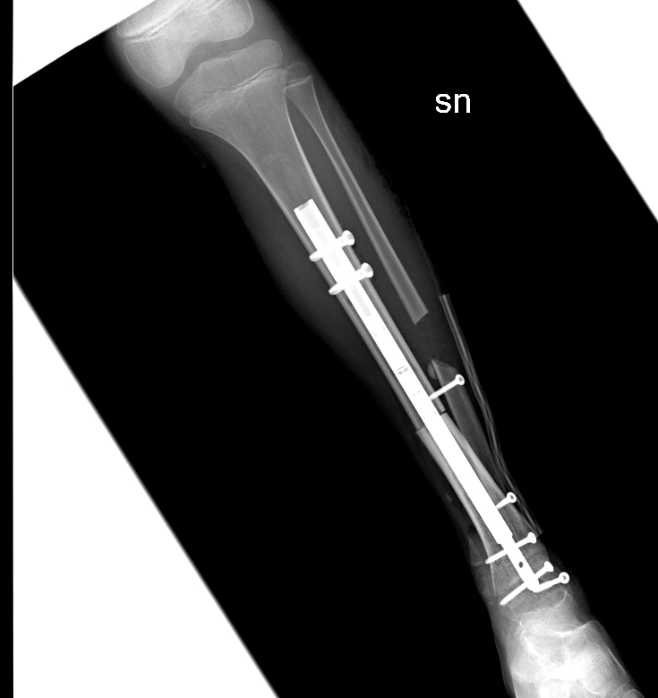

La bimba, dopo la diagnosi, è stata sottoposta a chemioterapia presso il reparto di Oncoematologia pediatrica dell’ospedale Regina Margherita (diretto dalla professoressa Franca Fagioli) e nei giorni scorsi è stata sottoposta all’intervento di asportazione del tumore e salvataggio della caviglia con ricostruzione con osso omoplastico da donatore e sintesi con un chiodo allungabile, in modo da permettere la regolare crescita dell’arto senza necessità di ulteriori interventi.

La tecnica eseguita rappresenta una assoluta novità in quanto il chiodo inserito per stabilizzare l’impianto permetterà nei prossimi anni anche la regolare crescita dell’arto permettendo l’allungamento al termine della maturazione scheletrica. La chirurgia è stata pianificata nei minimi dettagli dalle due équipes di medici ed ingegneri nelle settimane precedenti. Nonostante la pandemia da Covid-19 le cure legate a questo tipo di patologie si sono svolte regolarmente e senza ritardi. La bimba ora sta bene ed è stata appena dimessa.